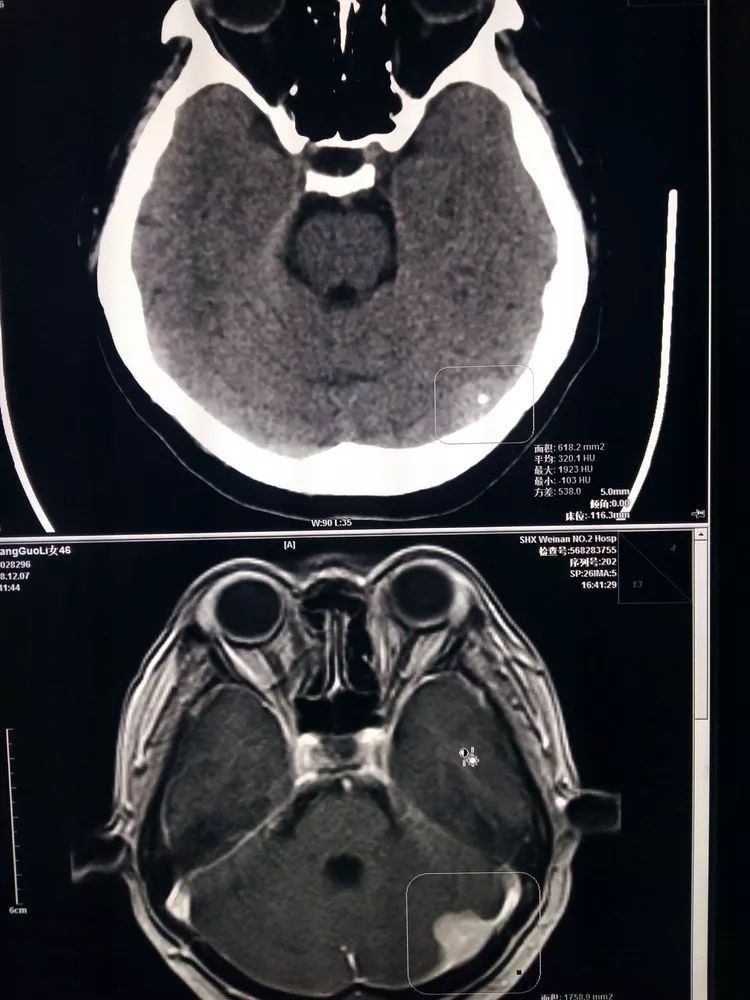

【影像讨论】肿瘤转移还是脑梗死? [病例帖]

进一步完善磁共振检查提示t1 相低信号,左侧脑室前角严重受压.

76岁脑瘤,请各位专业人士看一下磁共振图片,看看这个情况,分析一下.

哪位ct医生帮我看个ct片,75岁老人最近头痛去医院检查,医院说是脑瘤